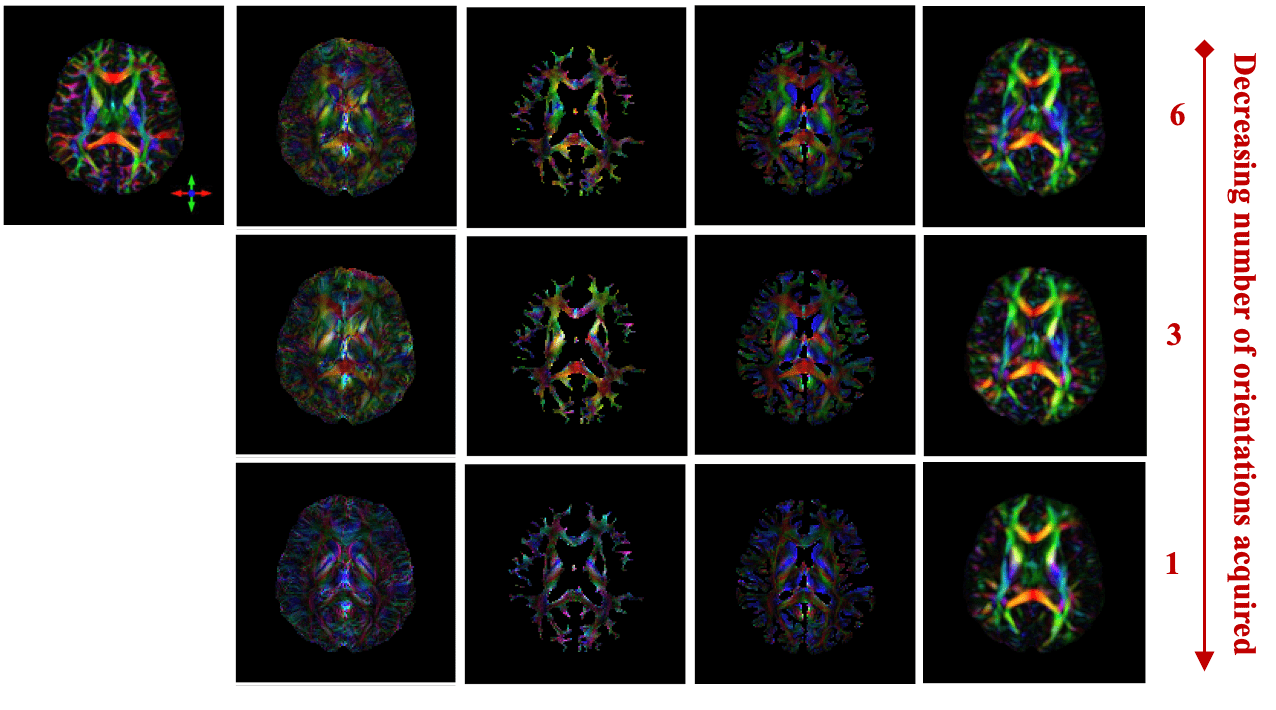

In Vivo Results

DTI

STIimag

[Li et al.]

MMSR

[Li and Van Zijl]

aSTI+

[Shi et al.]

DeepSTI

(ours)